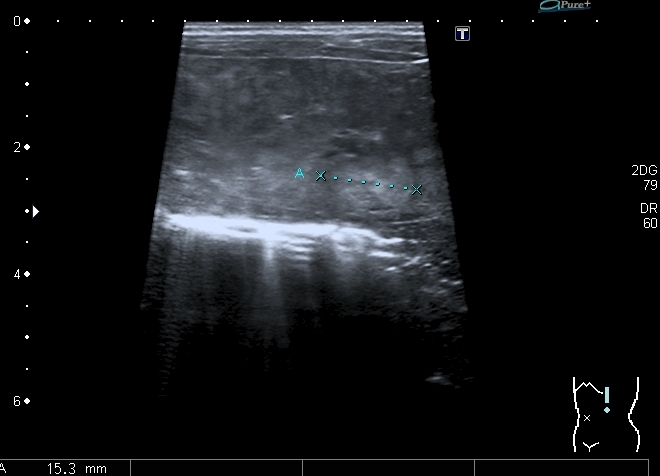

При УЗИ: печень резко увеличена, больше за счёт левой доли

Правая доля

Паренхима печени -гиперэхогенная , неоднородная, практически полностью замещена нодулярными образованиями, некоторые из них с "гало" и кальцификацией